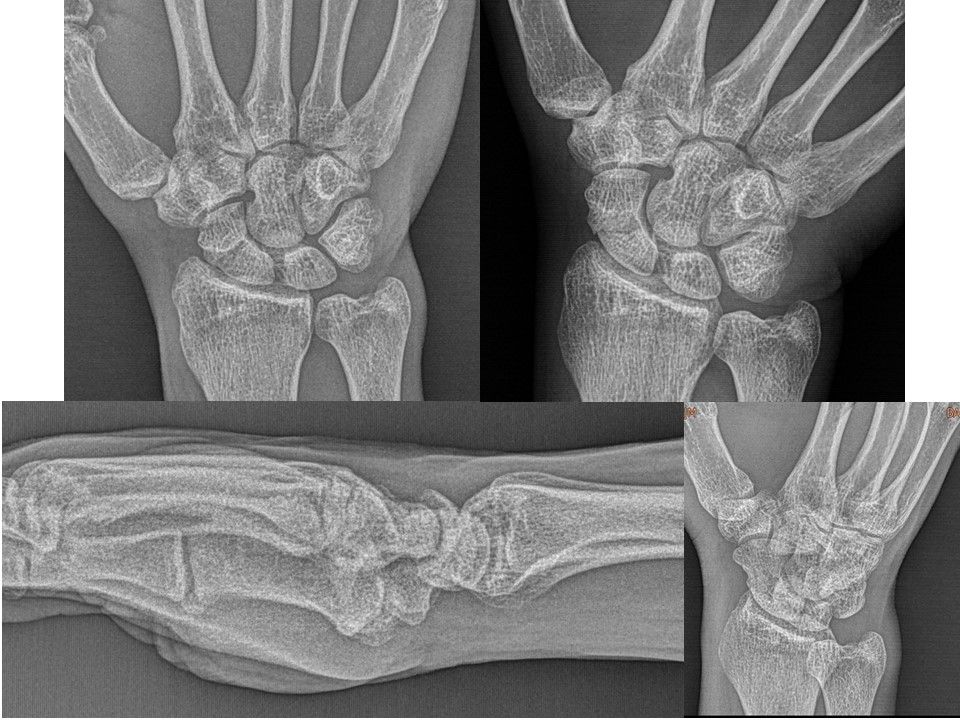

30 yr, male, fabric seller, right hand dominancy Ulnar sided right wrist pain felt occasionally History of 5. metacarpal fracture of right hand Watson shift test +, finger extension test +